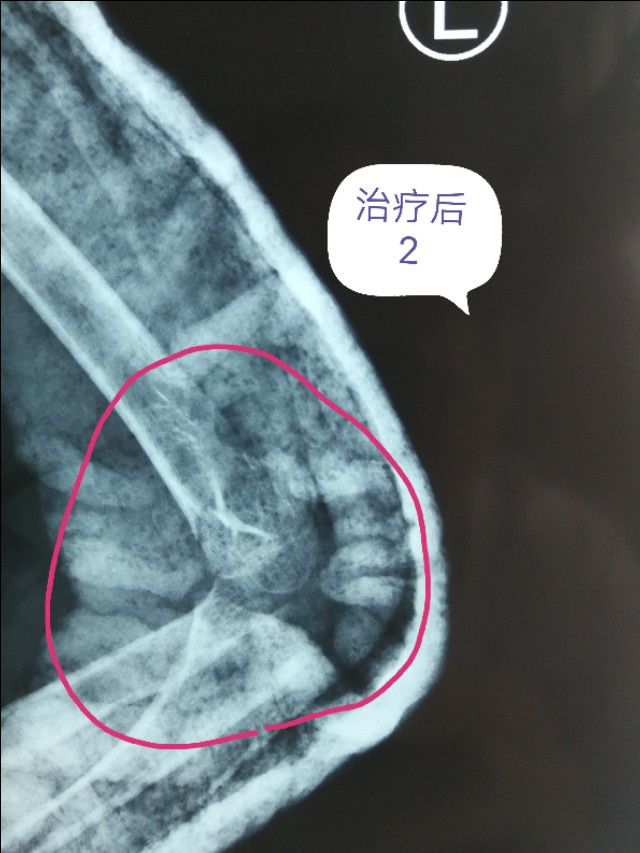

例二:闭合复位,经皮穿针固定